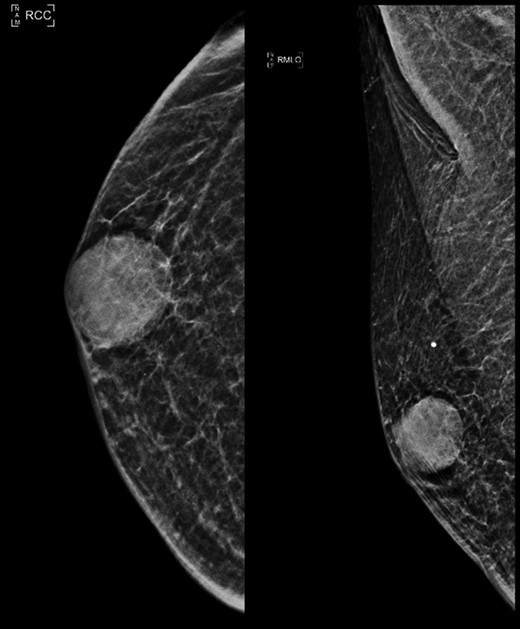

Bilateral mammogram (MMG) revealed a 2.1 cm × 2.1 cm well-circumscribed opacity in the retroareolar region of the right breast with mild indentation of the overlying skin. There were no associated calcifications or adjacent stromal distortion detected (Fig. 1).

Right mammogram craniocaudal (CC) and medial oblique (MLO) view.